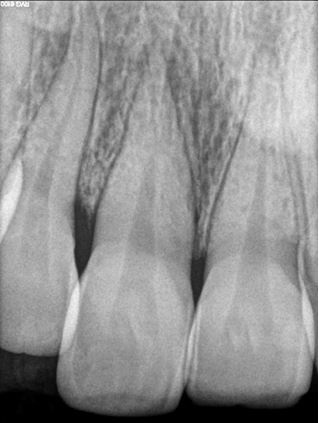

Management of intrinsic discoloration using walking bleach technique in maxillary central incisors

Introduction. Non-vital bleaching is a non-invasive technique to treat the intrinsic discoloration of teeth of several etiologies. Hydrogen peroxide and sodium perborate are commonly used bleaching agents.

Method. Maxillary central incisors were isolated with rubber dam and root canal treatment was performed. Barrier space preparation was done using a heated instrument. Glass ionomer cement was used a barrier material. Mixture of hydrogen peroxide and sodium perborate was placed in the canal and sealed with intermediate restorative material. After 1 week, the procedure was repeated to achieve the desired results.